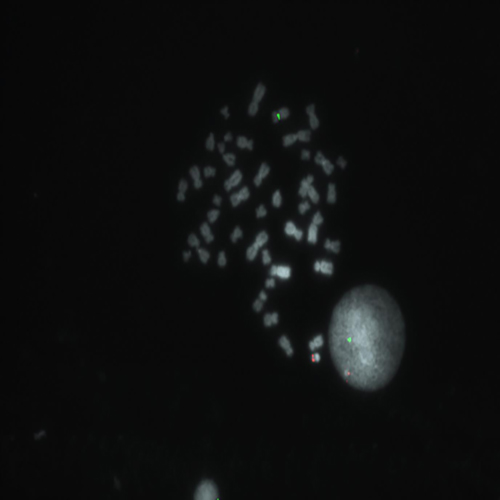

Kreatech FISH probes are the latest in advancements in FISH probes. Developed with the use of REPEAT-FREE technology, Kreatech FISH probes eliminate the use of Cot-1 or blocking DNA, providing a clearer background and a brighter signal.